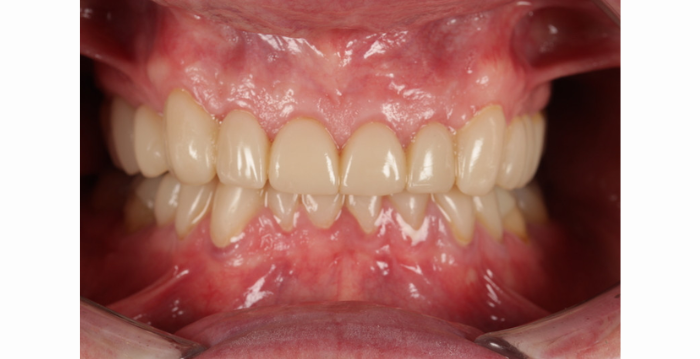

Il prodotto finale mostra il potere della stampa 3D nel settore dentale.

Il paziente è stato immediatamente soddisfatto del miglioramento dell’aspetto e del comfort. I controlli a due settimane, un mese, due mesi e tre mesi hanno confermato che il paziente si era adattato correttamente alla nuova dimensione verticale occlusale e alle riparazioni eseguite. Conservando lo smalto e riducendo al minimo la riduzione dei denti, questo approccio ha ridotto il rischio di pulpite (infiammazione o irritazione del nervo dentale) ottimizzando il comfort del paziente e la salute orale a lungo termine.